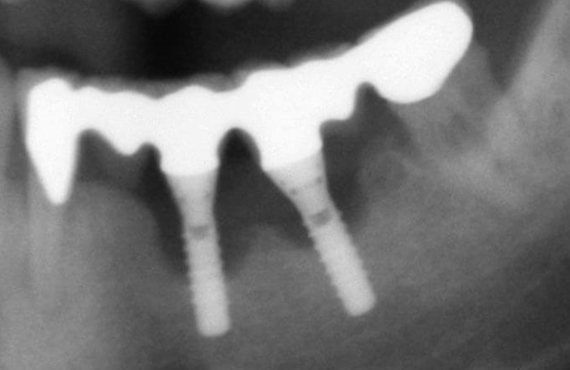

Prevention and Management of Dental Implant Complications – Latest Updates Part I

Success rates with Implant dentistry have been increasing with improving techniques.  More and more Implants are being placed with the advent of local courses and mini residencies, etc. As with any procedure, along with the...

The Growing Prevalence of Peri-implantitis: Diagnosis and Management of the Disease

Dental implants are highly predictable when treatment protocols are followed. Peri-implantitis is a disease that threatens implant survival long-term. For clinicians, there is no clear consensus on how to prevent and treat this fast-growing problem. This presentation will provide an...